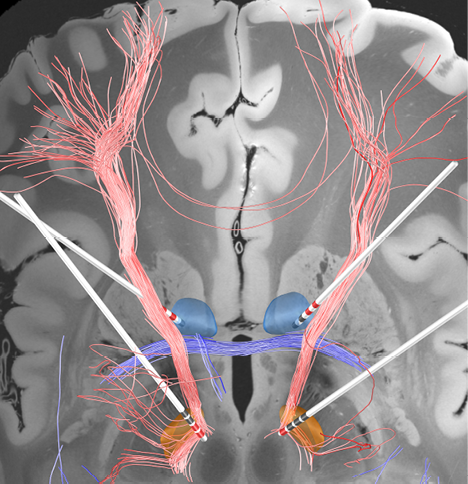

Figuur 1. Diepe hersenstimulatie bij patiënten met een obsessieve-compulsieve stoornis

Netwerkverbindingen (roze) tussen het stimulatieveld van de elektrodecontacten (rood) die tot de beste klinische resultaten leiden tijdens diepe hersenstimulatie van de nucleus subthalamicus (gele ovale structuur), of de overgang van de capsula interna tot de nucleus accumbens (blauwe ronde structuur).

(Figuur ter beschikking gesteld door Andreas Horn.)

In een studie met 22 patiënten met OCS die een ALIC/NAC-studie hadden ondergaan, werd aangetoond dat een goed resultaat correleert met het stimuleren van frontothalamische verbindingen die ventraal in de ALIC, net dorsaal van de overgang met de NAC, liggen.16 In een andere studie werden de klinische effecten gecorreleerd met een connectiviteitsanalyse in vier cohorten met een totaal van 50 patiënten: 30 hadden een ALIC/NAC-DBS, 14 een STN-DBS, en 6 een combinatie van ALIC/-NAC- en STN-DBS ondergaan. De resultaten toonden een common pathway tussen beide targets aan die correleerde met de beste klinische resultaten (zie figuur 1).17 Dit is een stap verder in de richting van netwerkmodulatie door DBS, in plaats van DBS met de focus op een welbepaalde anatomische structuur.